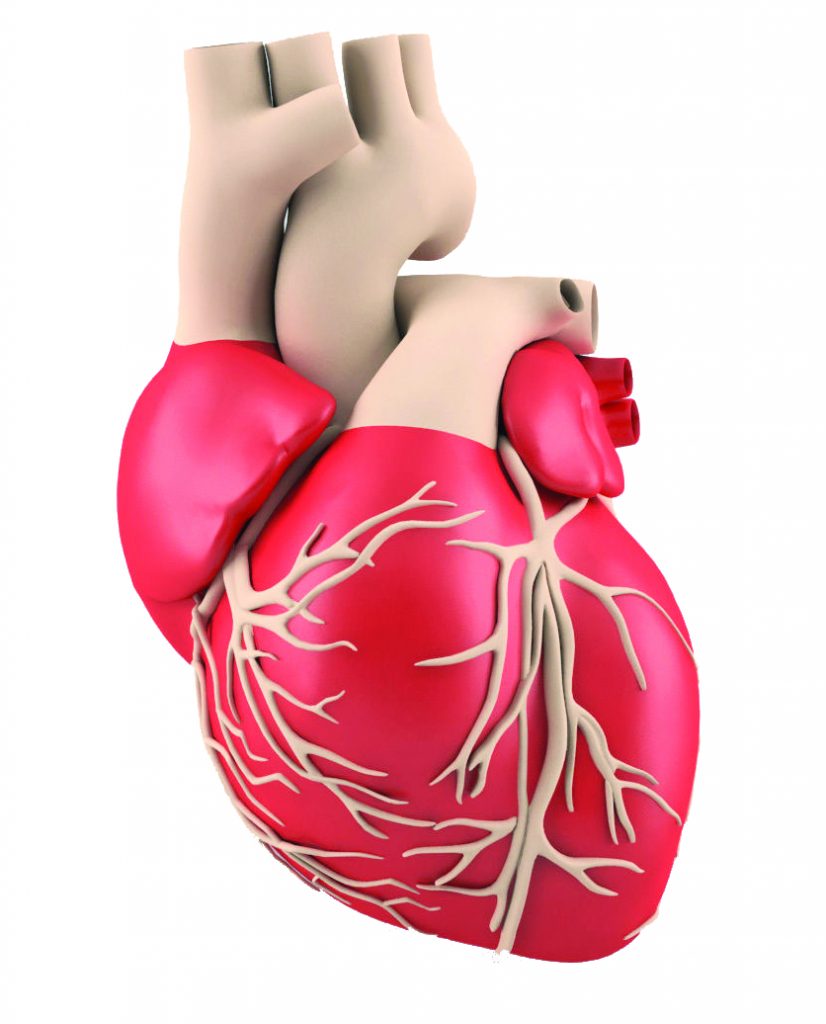

आफ्नो मुटुलाई हानि नपुर्याउनुहोस्

यदि तपार्इंले हरेक दिन ३० मिनेट मध्यम क्रियाकलाप गर्नुभएमा यसले मुटुरोग हुने जोखिमलाई ३० प्रतिशतले कम गर्दछ।

कोरोनरी रक्तनलीको रोग

कोरोनरी रक्तनलीको रोग भनेको के हो ?

कोरोनरी रक्तनलीको रोग भनेको यस्तो अवस्था हो जसमा मुटुमा आवश्यकताभन्दा कम मात्रामा रगत प्रवाह हुने गर्दछ। यसलाई इस्चिमिक मुटुरोग पनि भनिन्छ र यो हृदयाघात हुनुको प्रमुख कारण हो।

यो सामान्यतया मुटुको मांसपेशीमा रगत तथा अक्सिजन प्रवाह गर्ने कोरोनरी रक्तनलीहरू साँघुरो वा बन्द हुनाले लाग्ने गर्दछ।